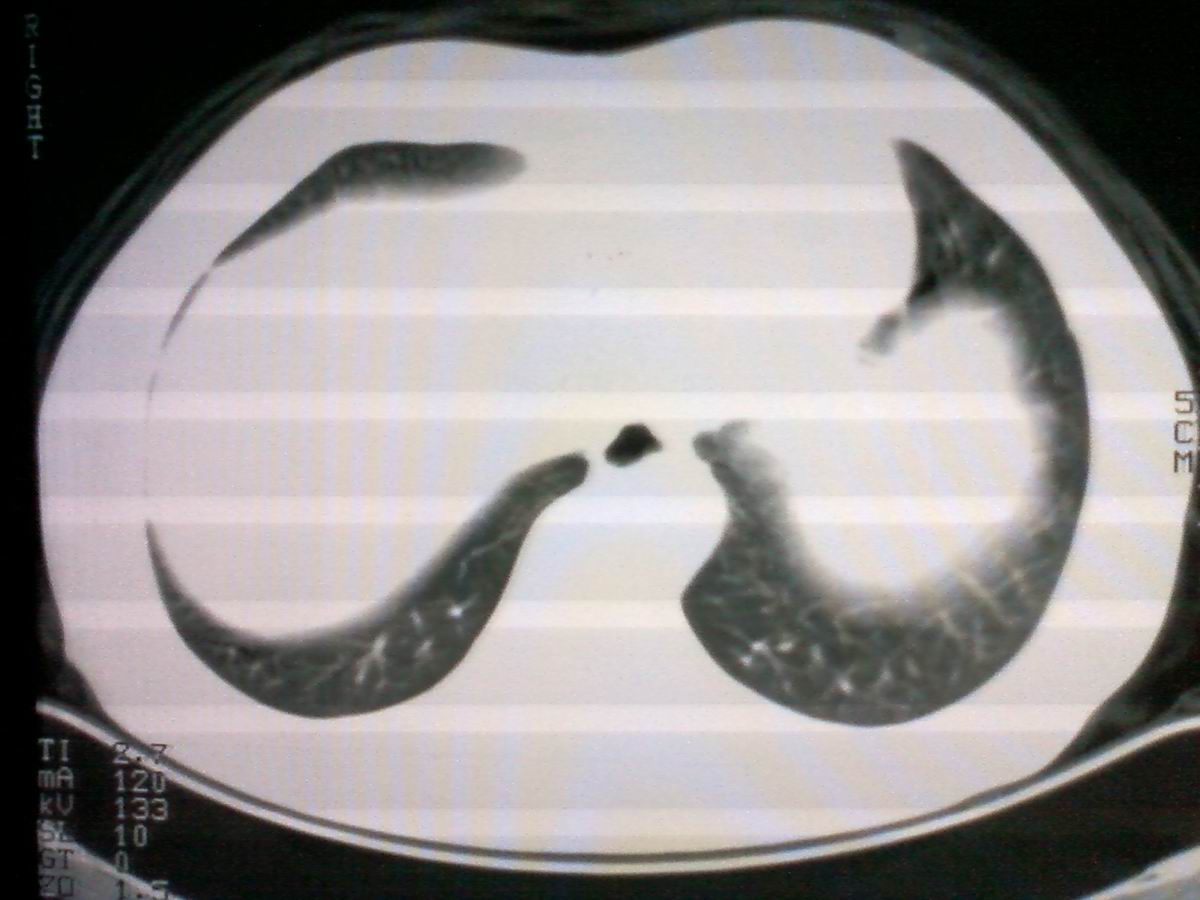

标题: CT25801:患者男性,65岁,临床提示双肺可闻及广泛罗音,看 [打印本页]

标题: CT25801:患者男性,65岁,临床提示双肺可闻及广泛罗音,看

气管后部见半圆形软组织密度病灶,考虑占位,建议气管镜除外鳞癌。

气管上段的肿瘤多为良性乳头状瘤,气管下段的肿瘤多为鳞癌,气管中段的良恶性各占一半。本例位于气管下段,先按恶性处理。不过纤支镜是免不了的。